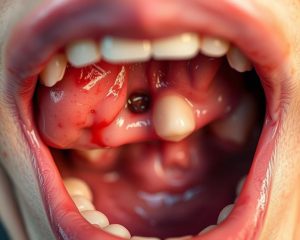

Ropnie w jamie ustnej to przykre stany zapalne, które objawiają się pojawieniem ropnych zmian w tkankach. Zwykle są wynikiem infekcji bakteryjnej, w której dochodzi do gromadzenia się ropy w miękkich tkankach lub pod kością. Te nieprzyjemne zmiany mogą wystąpić w różnych miejscach jamy ustnej, takich jak:

Główną przyczyną powstawania ropni są bakterie. Ich rozmiary mogą znacznie się różnić, a często towarzyszy im ból, obrzęk oraz zaczerwienienie otaczających tkanek. Jeśli nie zostaną odpowiednio leczone, mogą prowadzić do poważniejszych komplikacji, takich jak rozprzestrzenienie infekcji na inne obszary organizmu.

Ropień to obszar, gdzie gromadzi się ropa w wyniku infekcji. Organizm reaguje na obecność bakterii, co prowadzi do stanu zapalnego, a objawy obejmują obrzęk i zaczerwienienie tkanek w okolicy zmiany. Wydzielina ropna, która może pojawić się z ropnia, zazwyczaj sygnalizuje nasiloną infekcję, która wymaga pilnej interwencji stomatologicznej. Z mojego doświadczenia wynika, że zbagatelizowanie tych symptomów często prowadzi do poważniejszych problemów zdrowotnych.